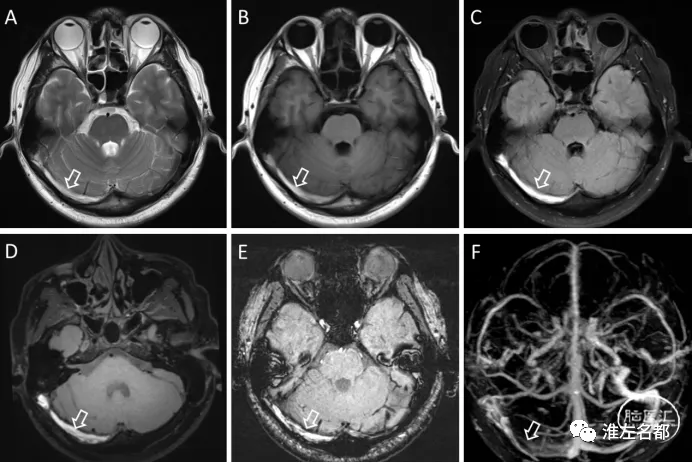

多个MRI序列可用于检测脑静脉窦血栓,其信号表现多样,信号高低与血栓形成的时间有关。 简单来讲,急性期的静脉窦血栓,在T1WI上呈等低信号,增强扫描无强化;亚急性期,T1WI呈高信号,增强扫描无强化;慢性期,T1WI呈等信号,增强扫描呈明显强化。三维黑血高分辨T1序列检测脑静脉窦血栓更为敏感和准确,其判断血栓形成大致时期的方法和常规T1WI序列是类似的。

右侧横窦亚急性血栓高信号(空白箭),图A是T2WI,图B是T1WI,图C是FLAIR,图D是T1-space平扫,图E是SWI,图F是增强MRV。